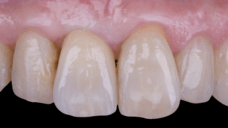

After an appropriate healing period, the definitive prosthesis was planned and delivered. A screw-retained zirconia crown was fabricated to ensure long-term durability, optimal esthetics, and retrievability. Zirconia was selected for its mechanical strength and excellent esthetic properties, blending seamlessly with the adjacent natural dentition in both form and color.

The final crown was designed to maintain the gingival architecture that had been shaped by the provisional. Special attention was paid to the emergence profile, contact points, and translucency to achieve harmony with the patient’s smile. The definitive restoration provided functional stability and esthetic integration, fulfilling the patient’s expectations for a fixed and natural solution.